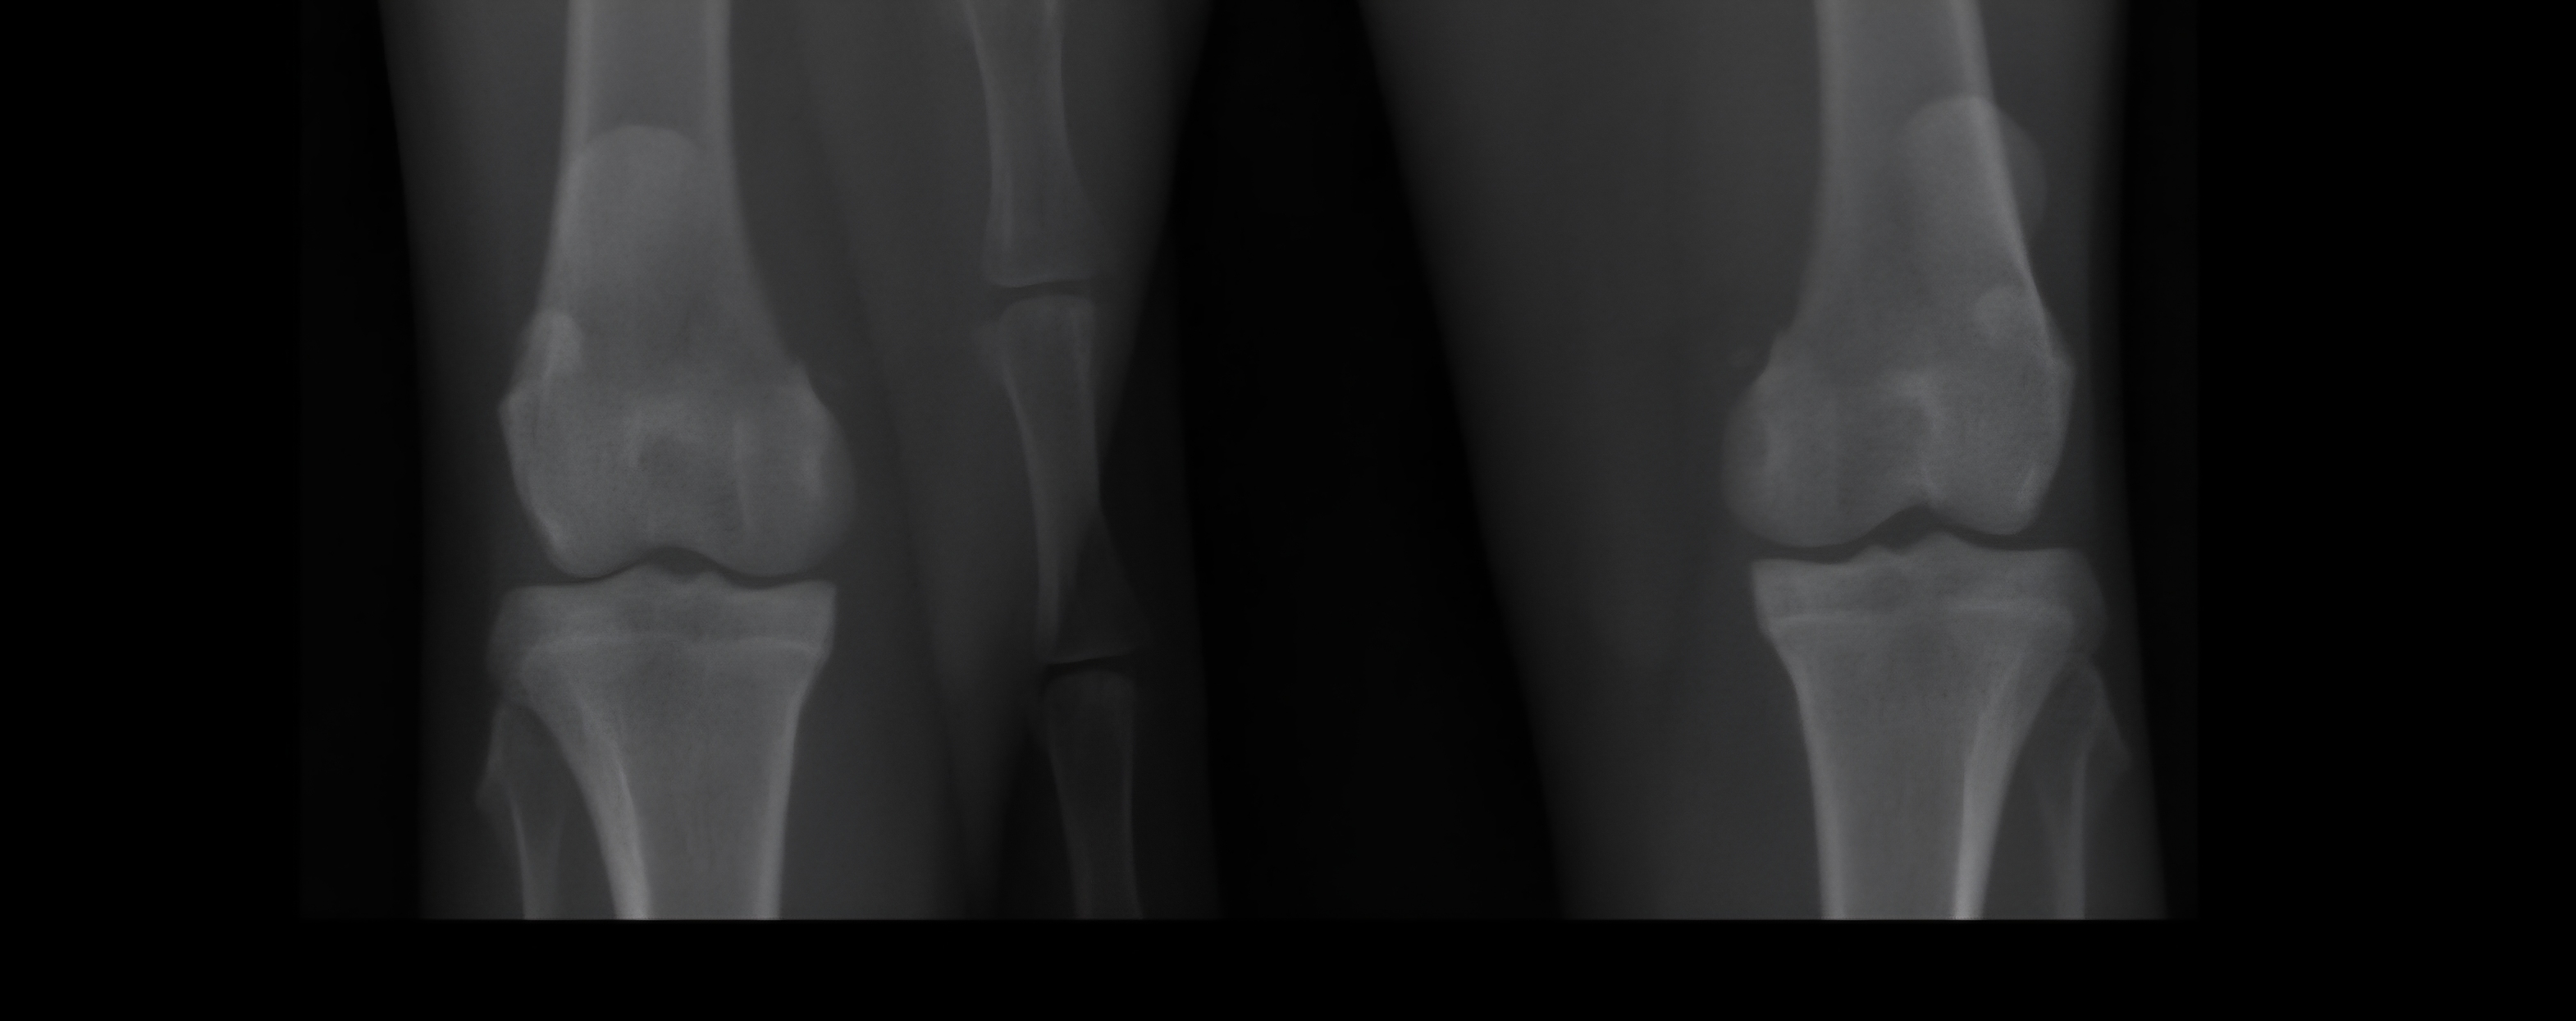

Knieen Jpg

Afbeelding – 732,3 KB

46 downloads

Download